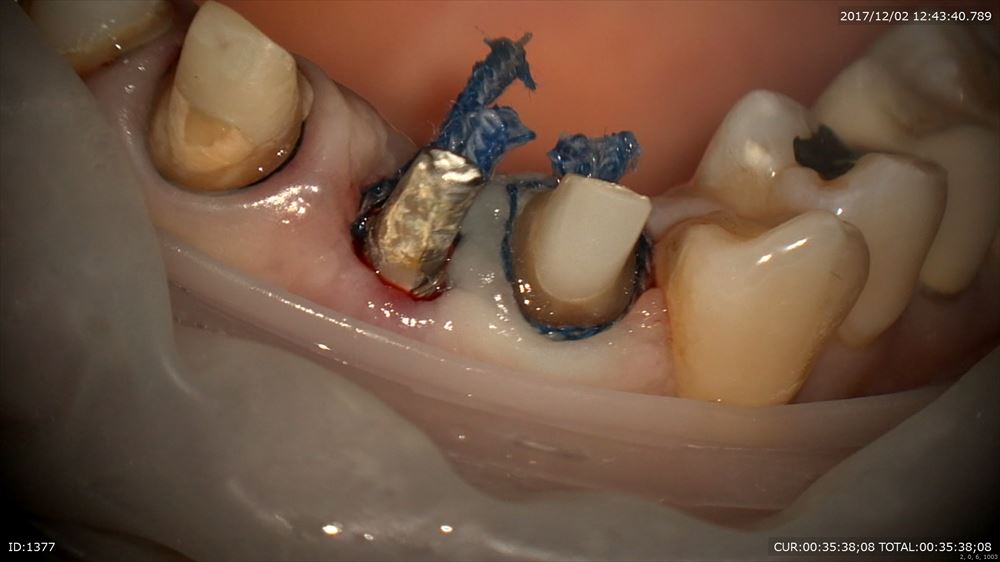

まず被せ物を外し

ここからコアを除去。金属が口に入ったり口を絶対に傷つけないためのラバーダム(必須!!)金属を飲んだら大変です。ラバーダムをしないで根管治療を行う事は当院では100%ありません。

やはりこんなに感染が